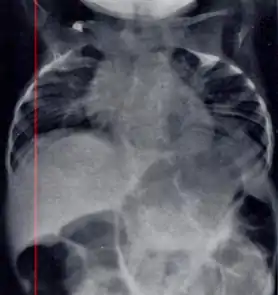

| Radiograph depicting typical skeletal features of Jarcho-Levin syndrome, subtype spondylothoracic dysplasia. Note fanlike configuration of the ribs, with extensive posterior fusion, along with multiple vertebral segmentation defects. | |

Spondylocostal dysostosis

In contrast to STD, the subtype spondylocostal dysostosis, or SCD features intrinsic rib anomalies, in addition to vertebral anomalies. Intrinsic rib anomalies include defects such as bifurcation, broadening and fusion that are not directly related to the vertebral anomalies (such as in STD, where extensive posterior rib fusion occurs due to segmentation defects and extreme shortening of the thoracic vertebral column).[6] In both subtypes, the pulmonary restriction may result in pulmonary hypertension, and have other potential cardiac implications.[7]